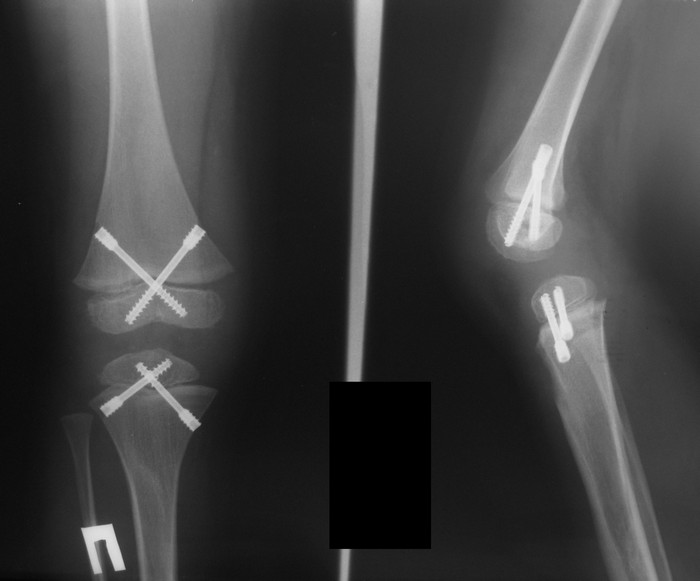

Спасибо, уважаемые коллеги, за комментарии. Взвесили все "за и против" и

остановились на эпифизеодезе. Теперь будем ждать результатов.